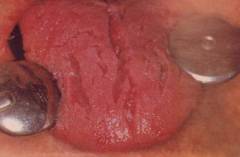

При грибковом поражении ротовой полости инфекция переходит на язык. Грибы находятся на поверхности слизистой и в норме, не вызывают воспаление языка (нормальная флора ротовой полости). Кандидоз развивается при сниженном иммунитете (например, у детей раннего возраста, стариков, ВИЧ-позитивных людей) и в результате лечения антибактериальными средствами или глюкокортикостероидными гормонами и цитостатиками. При снижении иммунных сил, на слизистой оболочке происходит клеточная реакция с задействованием нейтрофилов, моноцитов и эозинофилов. При этом грибковая инфекция проходит в слизистый слой. За счет воспалительного процесса происходит покраснение языка и его отек, а затем грибы начинают интенсивно размножаться, появляется белый или серый налет. Чем глубже поражение, тем больше разрастание грибов. При этом, как при любом грибковом поражении тканей, формируются аутоантитела (антитела к собственным клеткам организма), что позволяет грибкам проникать глубже в ткани. При поражении глубоких слоев слизистой языка и ворсинчатого эпителия возможно формирование ворсинчатого глоссита («волосатый язык»). При этом нитевидные сосочки значительно увеличиваются в размерах, приобретают темный цвет, ороговевают. При дальнейшем развитии инфекции, возможно попадание грибов в кровь, как результат, сепсис – распространение грибковой инфекции по всему организму и тяжелое состояние пациента. | ![]() Кандидозный (микотический глоссит). ![]() Катаральный глоссит ![]() Язвенный глоссит – характеризуется наличием язв, плотного белого налета, при снятии которого образуется кровоточащая рана ![]() Герптическая инфекция языка – характеризуется наличием пузырьков, которые после вскрытия оставляют болезненные эрозии. |